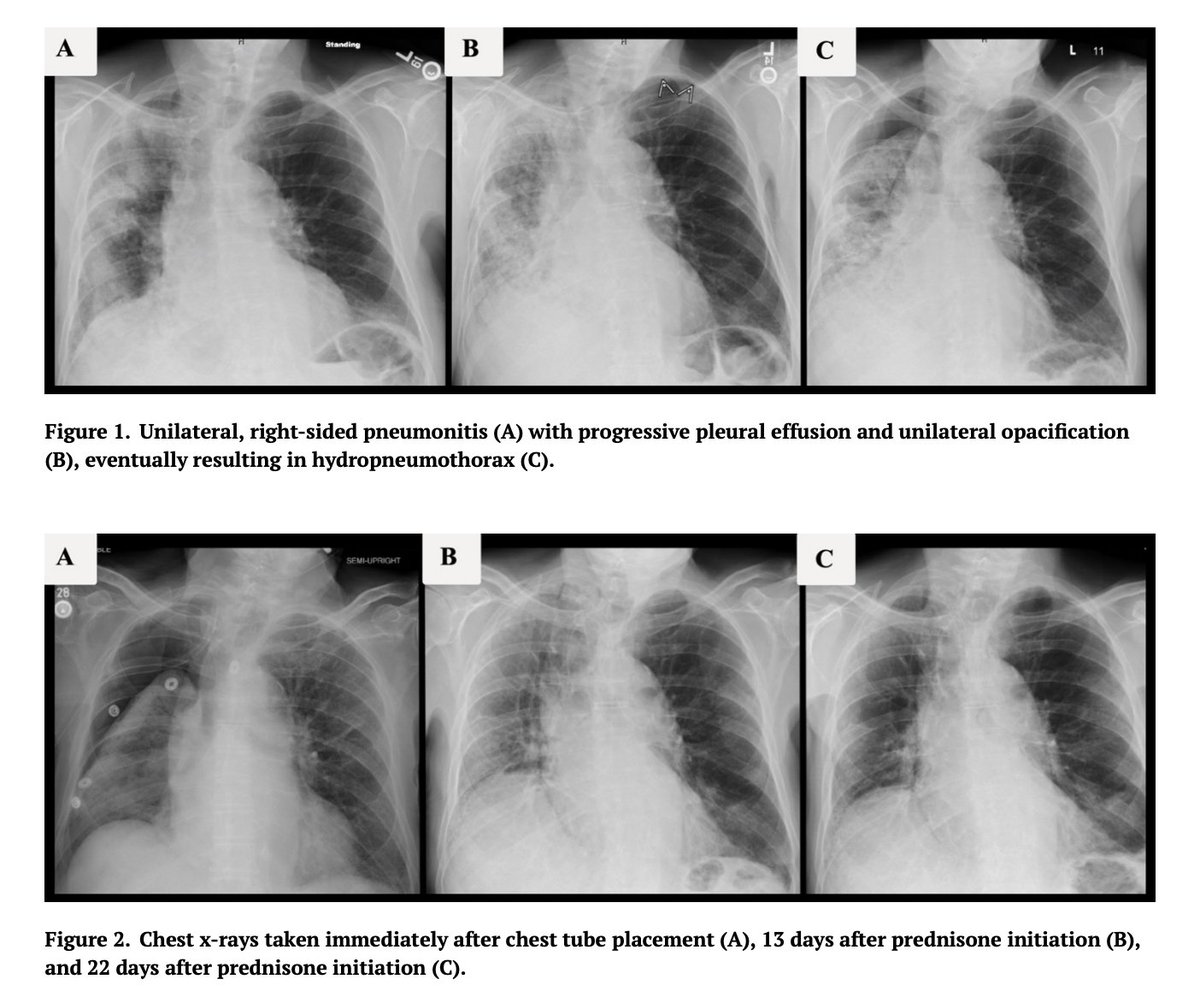

🫁 The radiographic presentation of ICI pneumonitis is quite diverse. On chest CT, findings similar to organizing pneumonia, NSIP, hypersensitivity pneumonitis, acute interstitial pneumonia, & sarcoid-like granulomatosis have all been described

🔴 Despite ↑ recognition that ICI pneumonitis can present unpredictably in temporality & chest radiography, focal/unilateral disease has rarely been reported

🔴 As a result, many clinicians only consider ICI pneumonitis in patients presenting w/ *bilateral* pulmonary disease

🚨 Given the high potential morbidity of untreated ICI pneumonitis, unusual radiographic features of ICI pneumonitis should be considered when assessing focal pulmonary infiltrates in patients on immune checkpoint inhibitors

🏁 In conclusion, the lack of symmetry in pulmonary radiographic abnormalities should not rule out ICI pneumonitis as a possible etiology of pulmonary disease in patients on immune checkpoint inhibitors